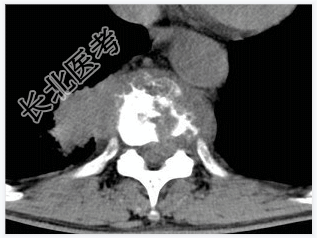

- [材料题] 男,32岁,低热、腰背痛,活动受限。

- 简答题1、结合CT检查,最可能的诊断是?

- 简答题2、椎体结核的典型症状是什么?